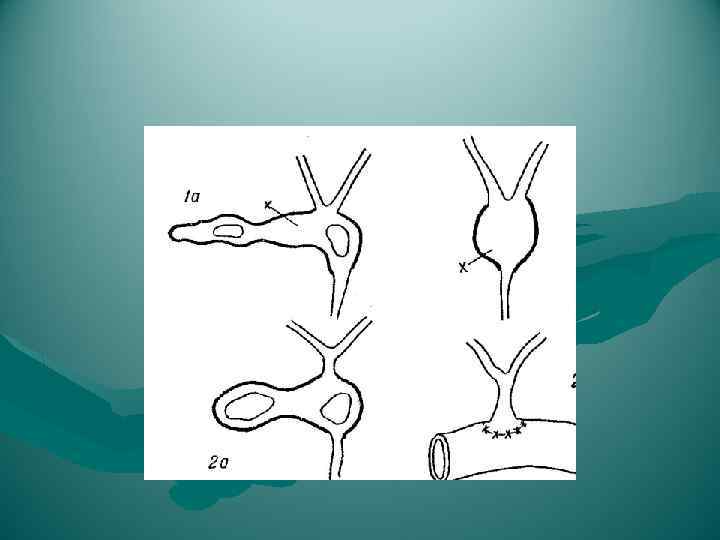

Варианты слияния протоков

Варианты слияния протоков